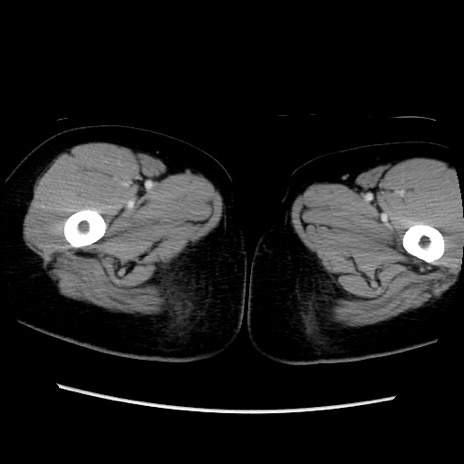

症例39(横断像)

【症例】40歳代女性

【主訴】上下腹部痛

【現病歴】2日目から下腹部痛あり。夜間は痛みで眠れなかった。昨日より上腹部痛と下痢が出現。臥位で痛みは軽快したため、休んでいた。本日になって臥位でも立位でも痛みが強くなってきたため救急要請。

【既往歴】子宮内膜症

【身体所見】部:平坦・軟、左上下腹部に圧痛あり、反跳痛あり。

【データ】WBC 21800、CRP 26.78